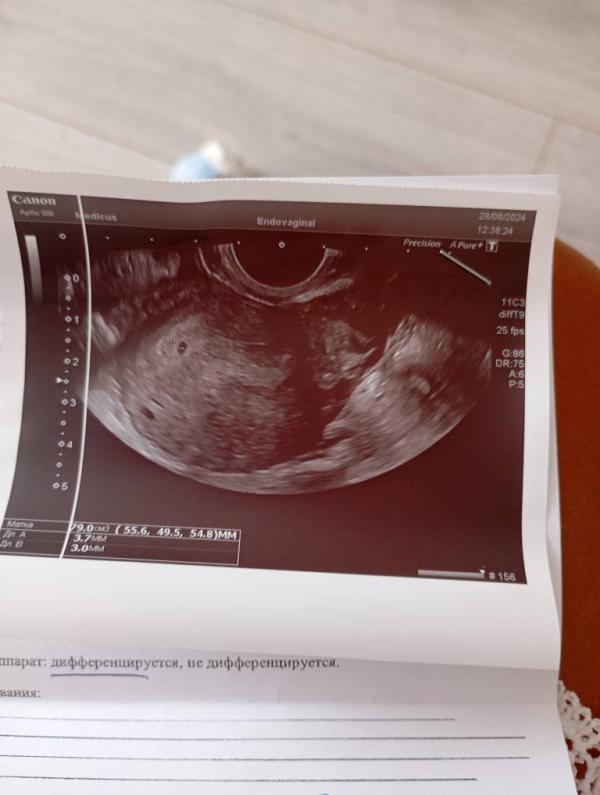

УЗИ моей малышки: сколько стоит платное обследование и что показало? Отзыв

Девочки сегодня ездила в платную клинику, делать узи😍моя маленькая прелесть 😍